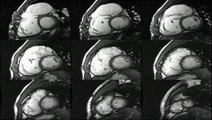

MRI sequences of a cardiac myxoma (a benign tumor)[1]